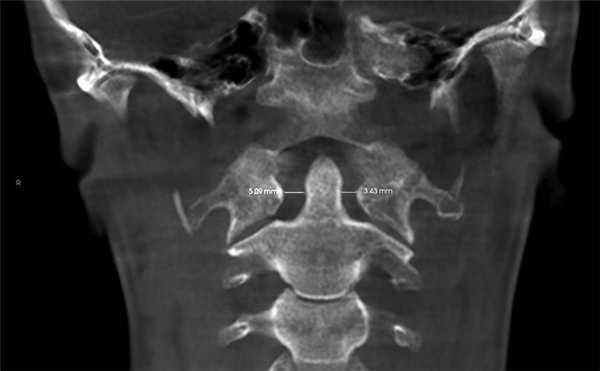

3. Оценка положения шейных позвонков (краниовертебральные функциональные пространства по M. Rocabado). В норме расстояние между C0—CI (затылочная кость и I шейный позвонок) и CI—CII (остистыми отростками I и II шейных позвонков) — 6,5±1—2,5 мм (рис. 8) [14].

4. Краниовертебральное центральное соотношение по M. Rocabado. На КЛКТ также есть возможность анализа ротаций первого и второго шейных позвонков. Измерение проводят от заднего бугорка первого шейного позвонка к зубу второго шейного позвонка, при этом большее расстояние свидетельствует о ротации CI в данную сторону (рис. 9).

Рис. 9. Ротация первого шейного позвонка (CI) вправо, так как расстояние между CI и зубом CII больше с правой стороны — 5,09 мм; слева — 3,43 мм.

Ротации шейных позвонков, уменьшение функциональных пространств служат причиной головных болей напряжения и лицевых болей, поэтому при обнаружении данных патологий необходим комплексный подход в лечении.